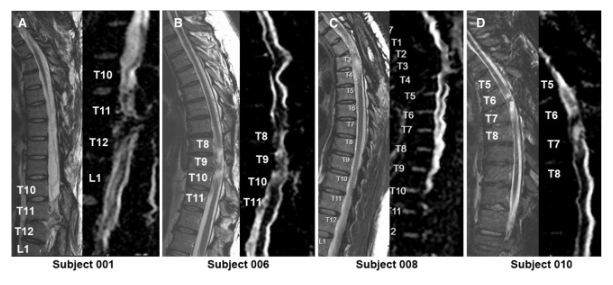

通過 MRI 和 DTI 成像評估動態(tài)反應

在 NSC 注射后,沒有放射學證據表明出現即時或延遲并發(fā)癥,包括術后即時或隨訪成像中沒有出現新的脊髓或軟組織水腫區(qū)域、增強或腫脹或積液。在純解剖或擴散張量序列中均未觀察到脊髓脊髓軟化癥的可見形態(tài)變化。

在所有四名患者中,彌散張量成像 (DTI) 成像顯示在損傷部位和損傷部位的前端/尾部脊髓束外觀穩(wěn)定,但未顯示重塑或纖維束造影改善的廣泛證據。

體格檢查顯示兩名患者的神經損傷水平 (NLI)、運動評分和感覺評分均有所改善。與細胞移植兩年后的神經系統(tǒng)評分相比,5 名受試者 001 的改善水平從兩年時的 2 個水平(改善)下降到五年時的?? 1 個水平。受試者 010 的改善在兩年和五年時均保持穩(wěn)定在 1 個水平的神經系統(tǒng)改善。